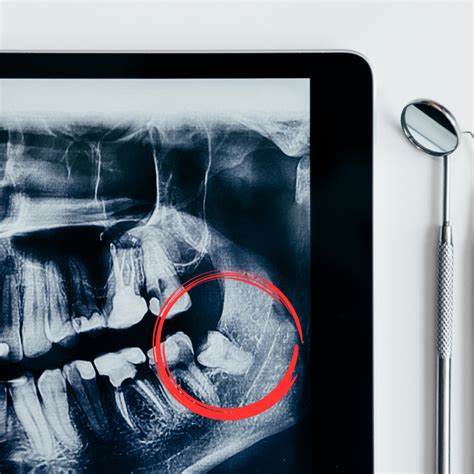

Extraemos las muelas del juicio cuando su permanencia supone un riesgo o un daño para la salud bucodental del paciente. Si no, podemos dejarlas con seguimiento. Es importante tomar la decisión con base en radiografías y la historia clínica.

¿Cuándo es Necesario Extraer las Muelas del Juicio?

Es necesario extraer las cordales cuando no tienen suficiente espacio para erupcionar, están impactadas, causan dolor, infecciones o daño a los dientes vecinos. Si no se extraen cuando causan problemas, pueden provocar infecciones, quistes, caries en dientes adyacentes o incluso desplazar la alineación dental.